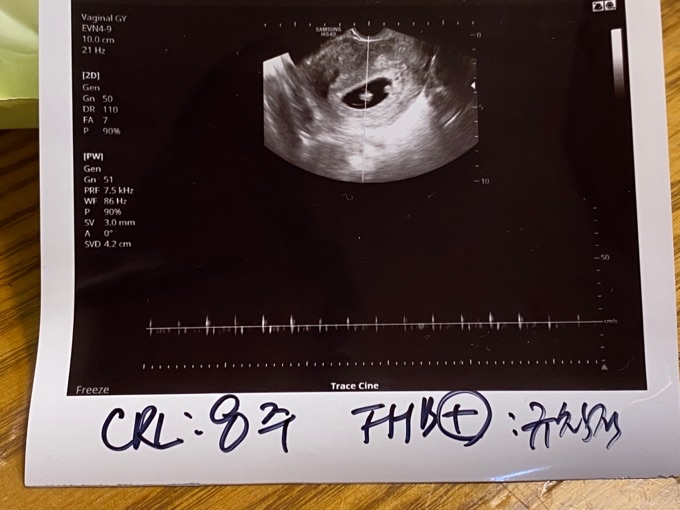

8주 초음파 아기가 작아보여요ㅠ

Community ViewIcon

제가 급히 타지역에 와 있게 되어있어서 다니던 병원을 못가고, 아기가 잘 있나 궁금한 마음에 집 근처에 여성의원을 가게 되었어요~ 본래 다니던 병원 기준으로는 8주1일이긴 한데, 오늘 병원에서 초음파를 보고나니.. 선생님께서는 아기가 잘 크고 있다 걱정할 것 없고, 심장도 규칙적으로 뛴다고 해주셨어요. 근데 늘상 다른 병원에서는 하던 심박수라던가 아기가 몇센티라던가 알려주시지 않더라구요😭 초음파 기계가 엄청 오래된 느낌이었는데,, 첨부한 사진으로 8주 정도의 크기라는 걸 어떻게 알 수 있는 걸까요? 이미지가 너무 작아서, 다른 분들 것과 비교도 잘 못하겠어요😭 그래도 잘 있다고 하면 걱정할 건 없는 거겠죠? 정말 임신초기 저절로 걱정몬 되는 것 같아요ㅠㅠ